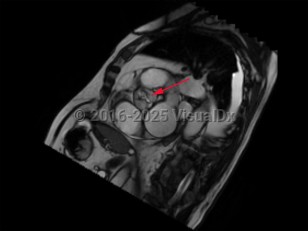

Aortic stenosis (AS) is the narrowing of left ventricular outflow through the aortic valve. It is the most prevalent cause of ventricular outflow obstruction, and it is increasing in prevalence as the population ages and life expectancy increases. While patients are generally asymptomatic in the presence of mild outflow obstruction, exertional dyspnea, chest discomfort, fatigue, dizziness, and syncope develop as the degree of obstruction progresses.

Contributing etiologies include calcification of the aortic valve cusps (most common in the elderly population), congenital abnormalities (ie, bicuspid aortic valve), rheumatic fever, chest radiotherapy, endocarditis, and alkaptonuria. Potential complications include heart failure, cardiac arrhythmias, infectious endocarditis, pulmonary hypertension, excessive bleeding, stroke, and other embolic events.